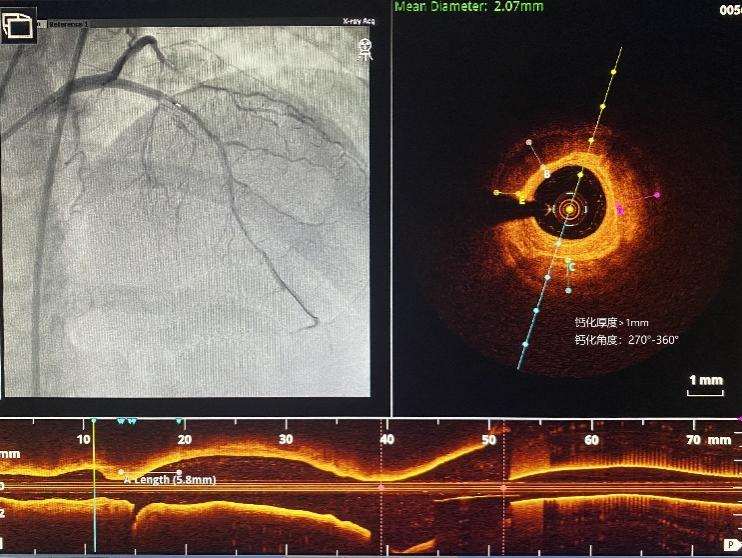

二次介入手术中,团队应用OCT检查血管,血管腔内的结构一览无余。可见LAD管腔内钙化角度大(270°-360°)、钙化非常厚(>1mm)、钙化弥漫(>20mm),钙化评分达到最高分值(CVI:4分),团队决定首选旋磨治疗。LAD应用1.25mm、1.5mm旋磨头以160000转/分的速率高速旋磨,重度狭窄的LAD最终被开通。严重狭窄的血管恢复了畅通,术后林女士胸闷、胸痛症状感到明显好转。